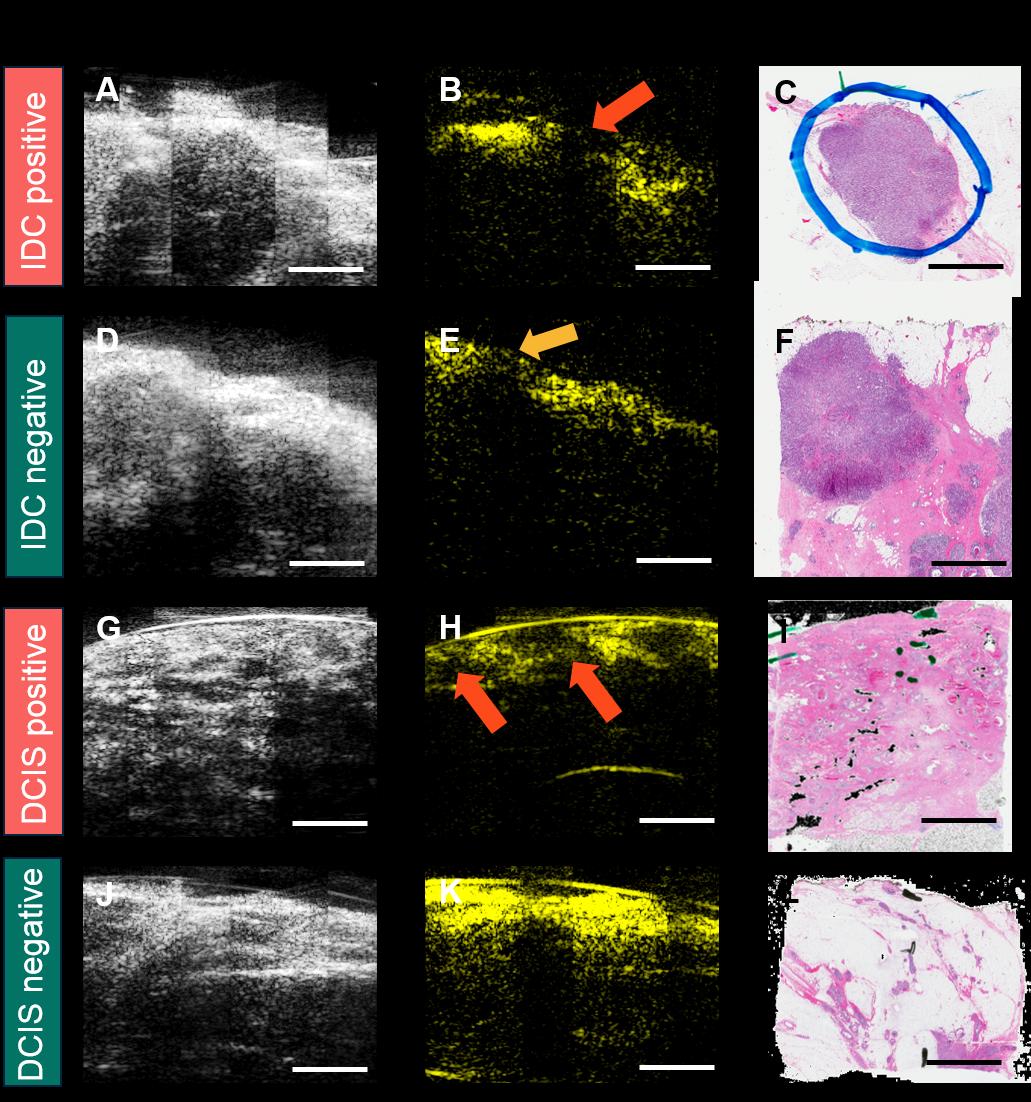

所有超声/光声图像均按照经乳腺成像专科培训的经委员会认证的放射科医生所推荐的相同标准进行采集和处理,并以相同的亮度水平和对比度尺度显示。前10例入组患者的数据被用作训练集以建立评估标准。训练数据集中具有不同特征的代表性图像如图3所示。第一列(图 3A‐D)为二维超声图像,显示了肿瘤团块(红色椭圆)、微钙化(组织内部的亮斑,橙色椭圆)、乳腺囊肿(紫色椭圆)以及纤维化(蓝色椭圆)。第二列(图3E‐H)为二维光声图像,显示了脂肪组织分布(绿色椭圆)。所有图像均通过第三列对应的苏木精和伊红(H&E)染色组织学图像(图3I‐L)进行确认[44,45]。根据外科学会肿瘤学分会‐美国放射肿瘤学会‐美国临床肿瘤学会2016年发布的最新共识指南,浸润性导管癌(IDC)要求墨水线清晰切缘,而导管原位癌(DCIS)则要求距组织表面至少2毫米清晰切缘[23]。因此,对于IDC,如果其表面未完全被脂肪组织覆盖(表面无光声信号),则判定为阳性切缘(图4A‐C),这与当前侵袭性乳腺切缘指南中关于墨水线切缘的标准一致。对于DCIS,若其表面未被至少2毫米厚的脂肪组织覆盖,或在距表面2毫米范围内发现微钙化,则判定为阳性切缘(图4G‐I)。切缘评估基于每份组织的全部超声/光声图像进行,只要至少有一个图像帧显示异常,该组织即被判定为切缘阳性。